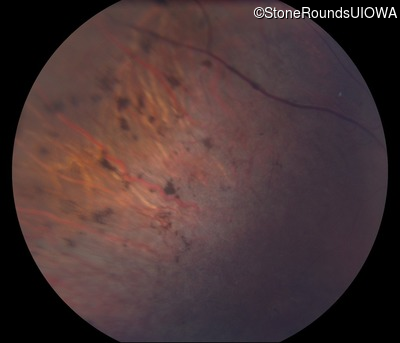

Fundus Photography - Right - 10/200

Exemplar